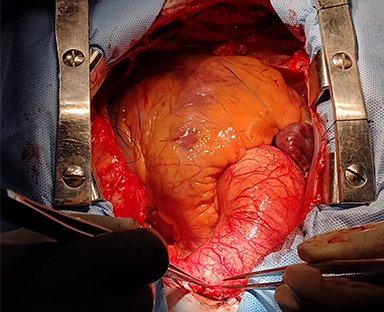

En esta sección se visualizarán cirugías reales en pacientes. Las fotografías por lo tanto

-si bien claras- en ocasiones privilegian la seguridad del paciente antes de

la exposición anatómica ideal.